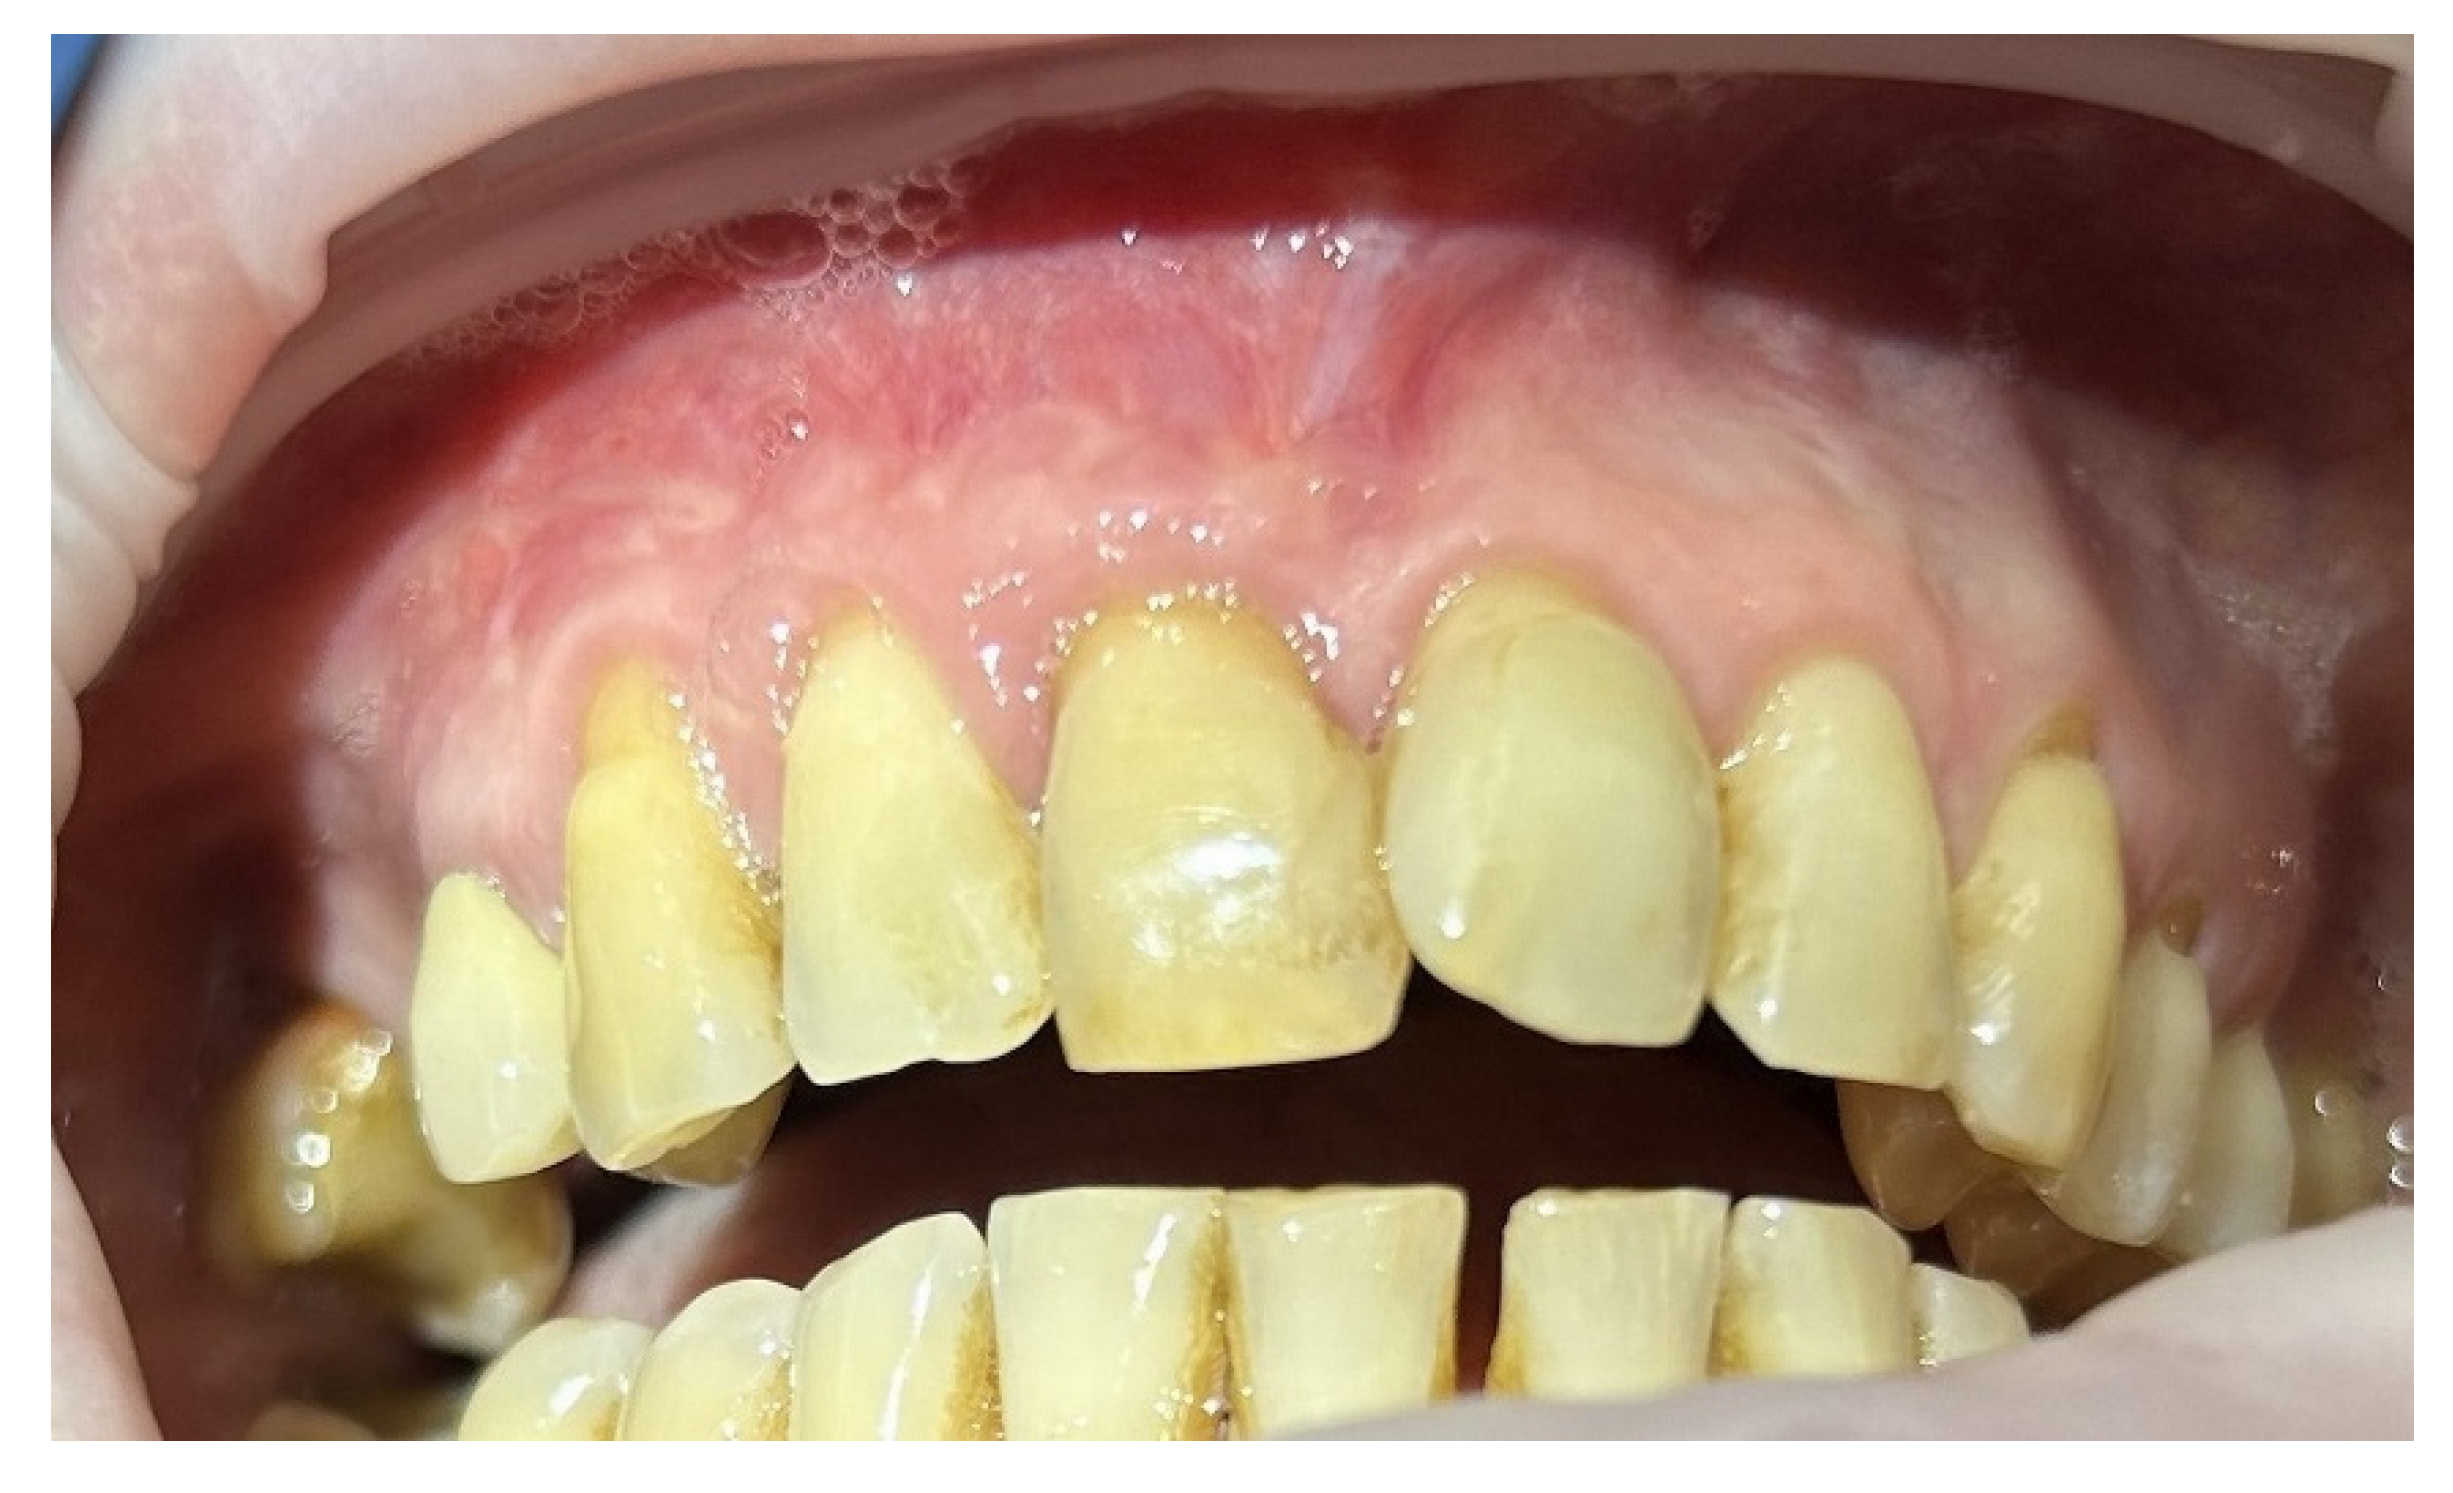

The functioning preserved teeth 1.3, 1.2, 1.1 and 2.1 were in stable condition (Figure 6).

Figure 6. Condition of causal teeth 2 years after enucleation of radicular cyst.